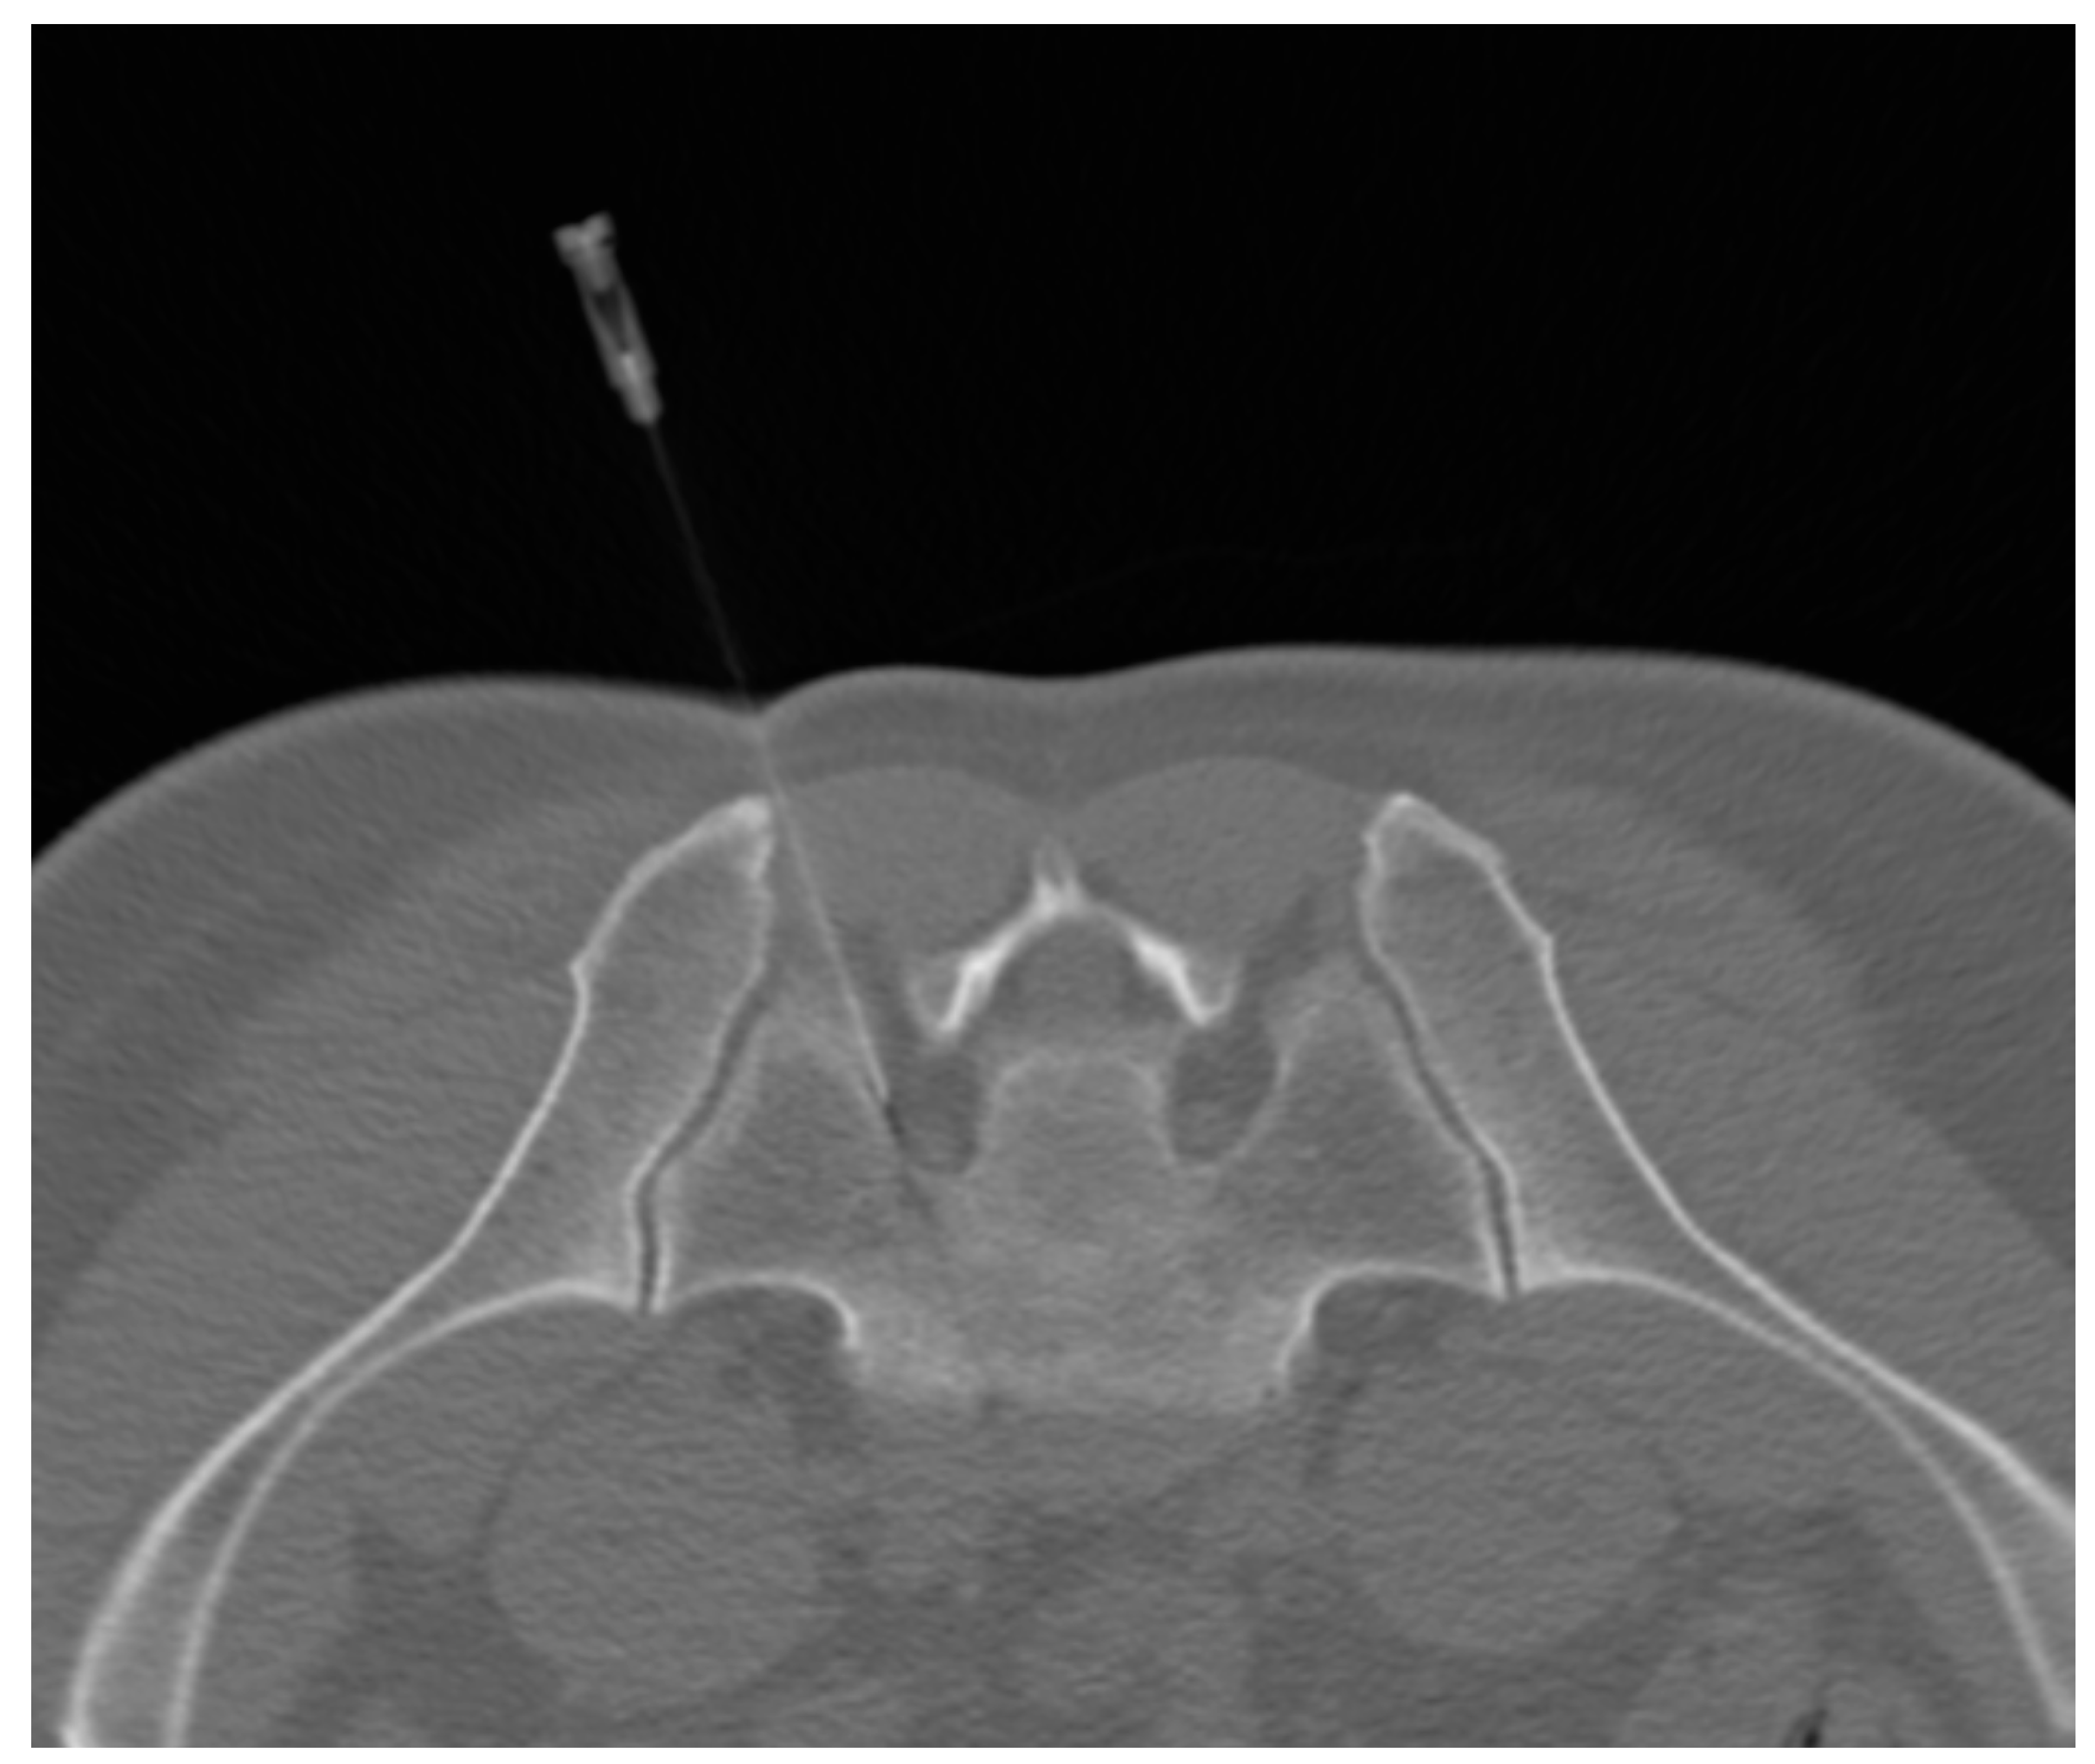

2.3. PRF–DRG Procedure